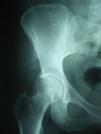

Dos años después del trasplante, la paciente consultó por dolor nocturno en cresta ilíaca derecha, que se irradiaba a la región trocanterea y a la extremidad inferior ipsilateral. En la exploración física se observó únicamente dolor a la palpación de la cresta ilíaca, la movilidad de cadera estaba conservada. Se realizó una Rx de pelvis que mostró una exostosis en la cresta ilíaca derecha (fig. 1), donde se había realizado la biopsia ósea, anomalía que no se observaba en la Rx previa al trasplante (fig. 2).